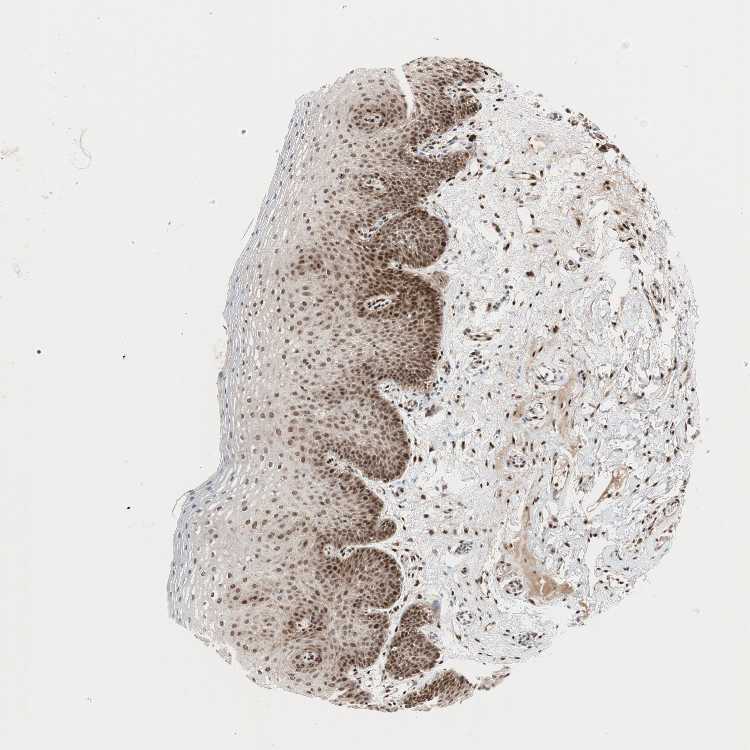

TISSUE PRIMARY DATA ORAL MUCOSA Show tissue menu

ORAL MUCOSA - Antibody stainingi

Antibody staining in the annotated cell types in the current human tissue is reported as not detected, low, medium, or high, based on conventional immunohistochemistry profiling in selected tissues. This score is based on the combination of the staining intensity and fraction of stained cells.

Each image is clickable and will lead to virtual microscopy that enables deeper exploration of all samples and also displays staining intensity scores, fraction scores and subcellular localization as well as patient and tissue information for each sample.

Antibody CAB004432

Squamous epithelial cells High